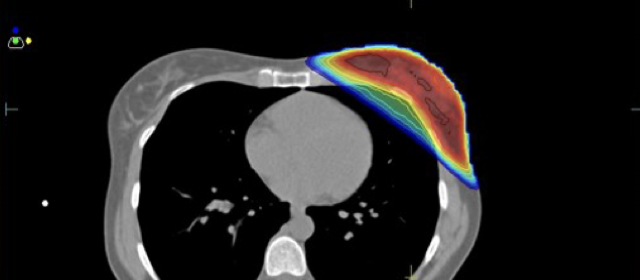

Κατανομή δόσης με την τεχνική ABC

Ελαχιστοποίηση δόσης στην καρδιά και τον πνεύμονα